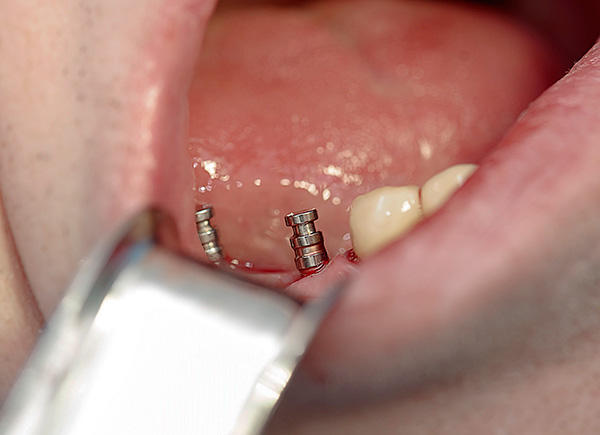

Gli impianti basali sono mostrati nella foto sotto: